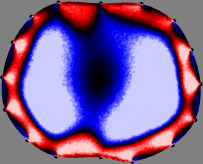

Figs. 3 and 4 compare the performance of the proposed FER method in (20) with the standard regularized least-squares method ((19) when is the identity matrix). The regularization parameter of the standard method was heuristically chosen for its best performance, and the parameter of the FER method was set to be one of three different values . The injection current was 1 mA at 100 kHz, and the frame rate was 9 frames per second. The reference frame at was obtained from the maximum expiration state. The measured data, , represent the voltage differences between each time and . The blue regions, which denote where conductivity decreased by inhaled air, increased during inspiration and decreased during expiration. The FER method with was clearly more robust than the standard method that produced more artifacts originated from the inversion process.

| Standard | |

||||||||||

| FER () | |